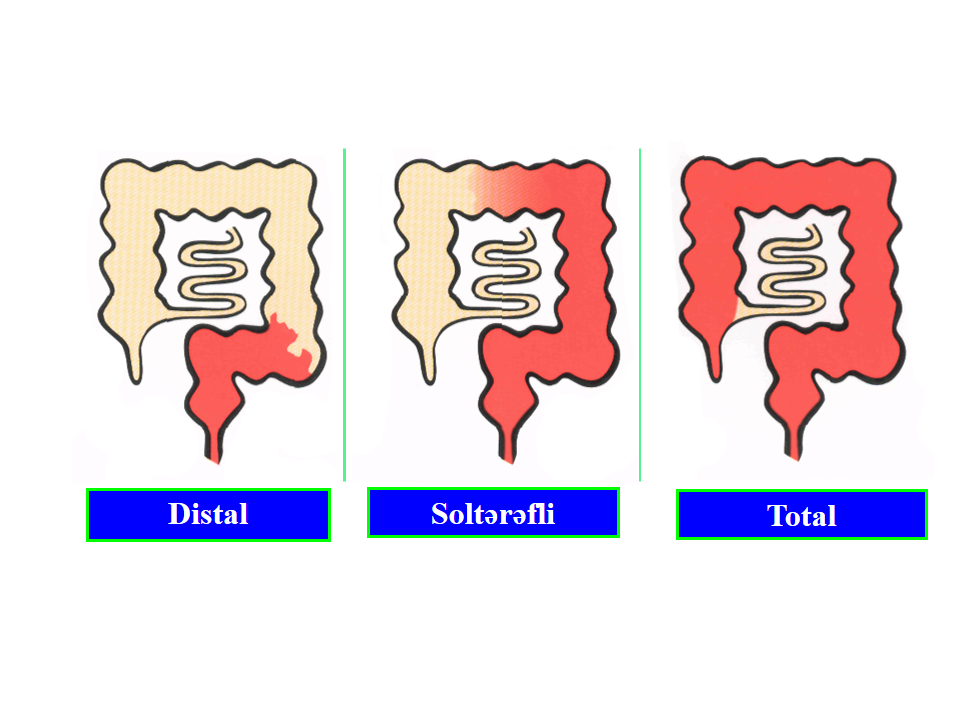

Xoralı kolit mədə-bağırsağın hansı hissəsini tutur?

Yalnız yoğun bağırsaqda olur.

Xoralı kolitin yayılma xüsusiyyəti necədir?

Daha çox rektum zədələnir, proksimala doğru yayılır, “sağlam aralar” olmur.

Kolon tamamən iltihabi prosesə cəlb olunubsa nə adlanır?

Pankolit